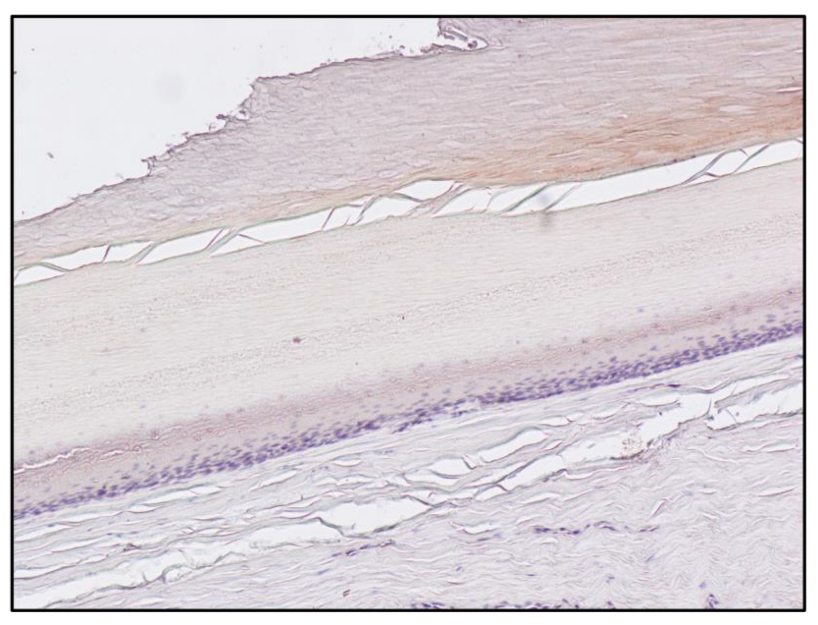

| Subject B (Figure 2) | 1,228,800 | 26.049 |

| Subject B matrix | Instrument | Morphine | 6-MAM | Codeine | Methadone | EDDP |

| Blood | GC-MS | 360 ng/ml | Negative | Positive | Positive | Positive |

| Pubic hair | UHPLC | 1.60 ng/mg | 0.44 ng/mg | Positive | Positive | Positive |

| Fingernail | UHPLC | 1.23 ng/mg | 1.18 ng/mg | Positive | Positive | Positive |